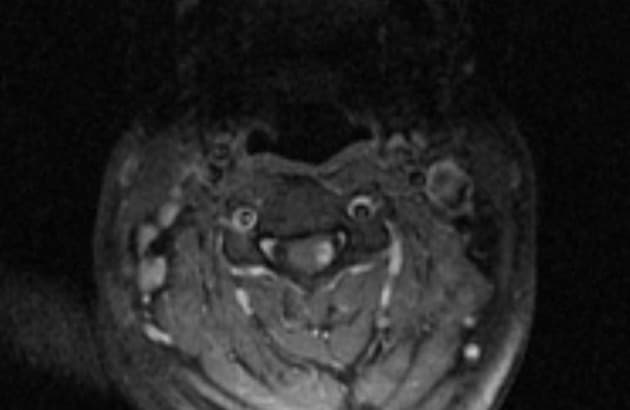

Chụp cộng hưởng từ (MRI) cho thấy các đặc điểm điển hình của bệnh xơ cứng rải rác. Ngoài ra, một số tổn thương có tín hiệu tăng trên hình ảnh T1 (T1 hyperintense).

- Các tổn thương rải rác, dạng vệt hoặc hình tròn, tăng tín hiệu trên hình ảnh khuếch tán (diffusion-weighted imaging), khu trú chủ yếu ở vùng chất trắng quanh thất (periventricular white matter), chất trắng ở bán nguyệt (juxtacortical white matter), thân gai thị – giao thoa thị giác (optic radiation – optic chiasm), và thân não (brainstem) – phù hợp với đặc điểm của xơ cứng rải rác (multiple sclerosis).

- Đa giác Willis (Circle of Willis) và các động mạch não trước (anterior cerebral artery), động mạch não giữa (middle cerebral artery), động mạch não sau (posterior cerebral artery) thông thoáng, không thấy tắc mạch (occlusion), bóc tách (dissection) hay tuần hoàn bàng hệ (collateral circulation) bất thường.